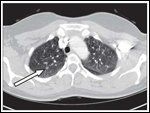

FIGURE 4

Pulmonary Nodules-

Pulmonary nodules seen on chest CT including 6-mm right upper lobe nodule (arrow). CT = computed tomography.

Multiple subcentimeter nonspecific nodules are present in both lungs (Figure 4). The largest nodule measures 6 mm. On the most recent chest CT, a 3-mm right lung nodule might be new or not seen previously due to the nodule’s small size and differences in slice selection.